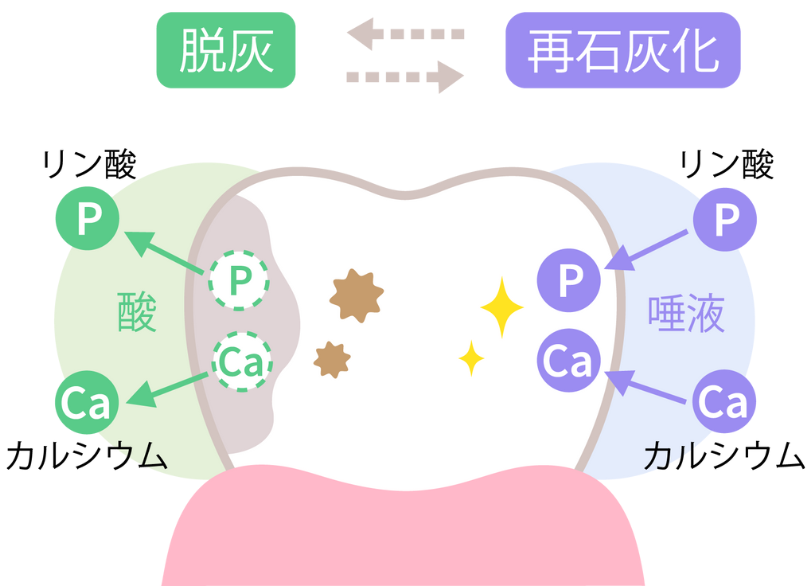

菌が作り出す「酸」によって歯が溶ける

ミュータンス菌は糖分を分解する過程で「酸」を産生します。

この酸によって歯の表面を覆う硬いエナメル質から、カルシウムやリンといったミネラル成分が溶け出してしまう。

この現象を「脱灰(だっかい)」と呼びます。

食事のたびにお口の中ではこの脱灰が起きています。

一方で私たちの唾液には酸を中和し、溶け出したミネラルを歯の表面に再び取り込んで修復する「再石灰化(さいせっかいか)」という素晴らしい働きがあります。

通常であればこの「脱灰」と「再石灰化」のバランスが保たれることで歯の健康は維持されています。